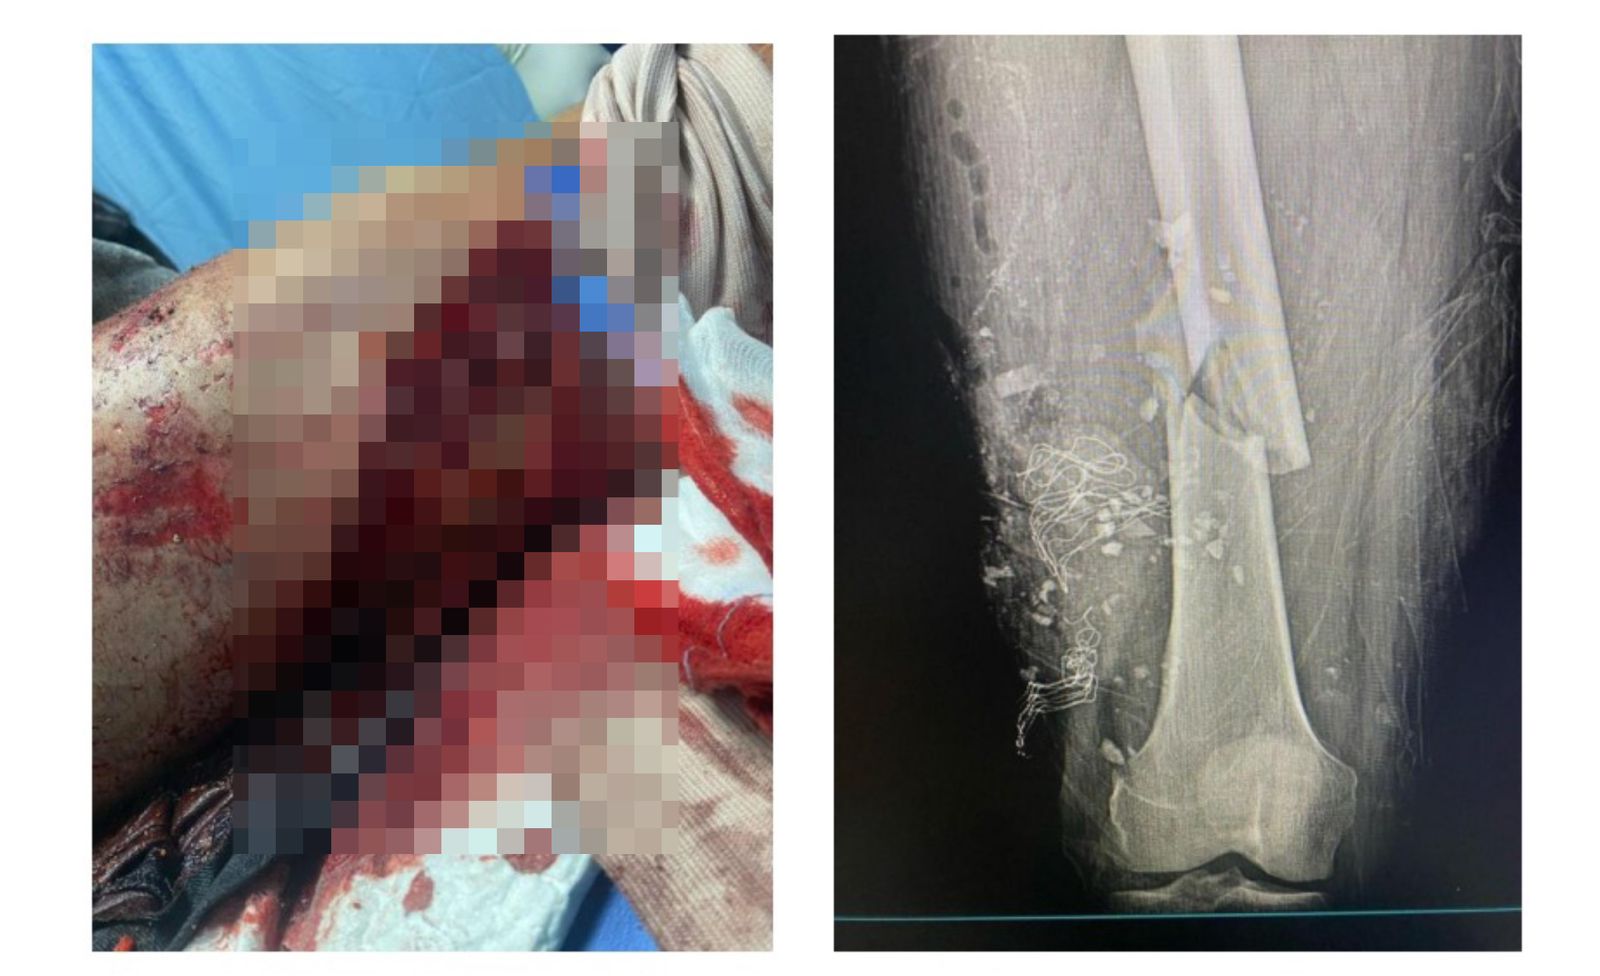

Redacción.- Maribel Espaillat, imputada junto a su hermano Antonio Espaillat, por el colapso del techo de la discoteca Jet Set que dejó un total de 235 muertos y más de 150 heridos, presentó como evidencias durante la audiencia de medida de coerción, pruebas médicas y fotografías que documentan las lesiones que ella misma sufrió en la tragedia ocurrida el pasado 8 de abril.

Como parte de los elementos introducidos por sus abogados, se incluyó un certificado médico emitido por el doctor Francisco R. Mella Garrido, cirujano ortopedista, que detalla el ingreso clínico de Espaillat, según el documento, diagnosticada con politraumatismo por heridas traumáticas en la cabeza, extremidades superiores e inferiores.

El informe estuvo acompañado de imágenes que muestran las heridas físicas sufridas por Espaillat, con el objetivo de demostrar que ella también fue víctima directa del colapso.

Asimismo, la defensa también aportó documentación médica relacionada con su esposo, Héctor Danel Bera Pichardo, quien tuvo que ser intervenido quirúrgicamente en dos ocasiones a causa de las heridas sufridas la noche de la tragedia. Según consta en el certificado, Pichardo fue sometido recientemente a una nueva operación de fémur, por lo que, alegaron los abogados, este requiere cuidados especiales y la presencia de su esposa Maribel Espaillat.